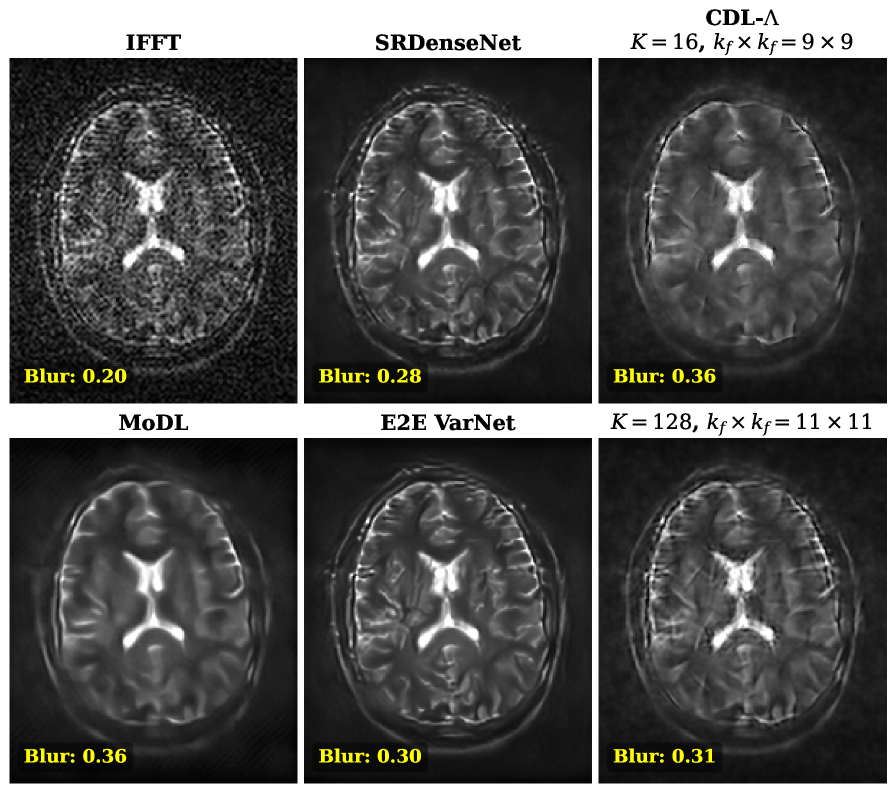

Comparison to Other Methods: Figure 4 shows a visual comparison of the adjoint reconstruction, MoDL, E2E VarNet, SRDenseNet, and the investigated CDL-𝚲\boldsymbol{\Lambda} using K=64K=64 filters of size kf×kf=11×11k_{f}\times k_{f}=11\times 11 for a brain and knee MR image, together with their respective error images and image metrics.

Refer to caption

Fig. 4: A comparison of MoDL [1], E2E VarNet [19], SRDEnseNet [7] and CDL-𝚲\boldsymbol{\Lambda} method (K=64,11×11K=64,11\times 11-kernels) on in-distribution brain MR data (left, σ2=0.3\sigma^{2}=0.3) and out-of-distribution knee MR data (right, σ2=0.2\sigma^{2}=0.2).

Fig. 6: In vivo T2-weighted brain MR image: MoDL, E2E VarNet and SRDenseNet, and the CDL-𝚲\boldsymbol{\Lambda} with the improved NETΘ\mathrm{NET}_{\Theta} (V3), once with K=16K=16 filters of size kf×kf=9×9k_{f}\times k_{f}=9\times 9, and once with K=128K=128, kf×kf=11×11k_{f}\times k_{f}=11\times 11. Note how the use of a larger dictionary at inference, which was not used in training, leads to a sharper result.

Application to In Vivo Data: Figure 6 shows a comparison of the methods applied to a T2-weighted in vivo image. Since no target image is available, the blur metric (the higher, the blurrier) is displayed together with the reconstructed image. All methods successfully removed noise and improved the resolution, producing comparable results, with MoDL exhibiting a slight tendency to oversmooth image details. Observe also how CDL-𝚲\boldsymbol{\Lambda} in this case benefits from using a larger dictionary at inference (K=128K=128) that leads to a sharper result.